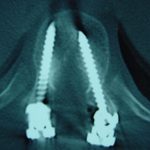

Εικ. 4: Μετεγχειρητική προσθιοπίσθια (α) και πλαγία (β) ακτινογραφία της θωρακο-οσφυικής μοίρας της σπονδυλικής στήλης.

Παρατηρείται η σταθεροποίηση της σπονδυλικής στήλης με σύστημα διαυχενικών κοχλιών και ράβδων.